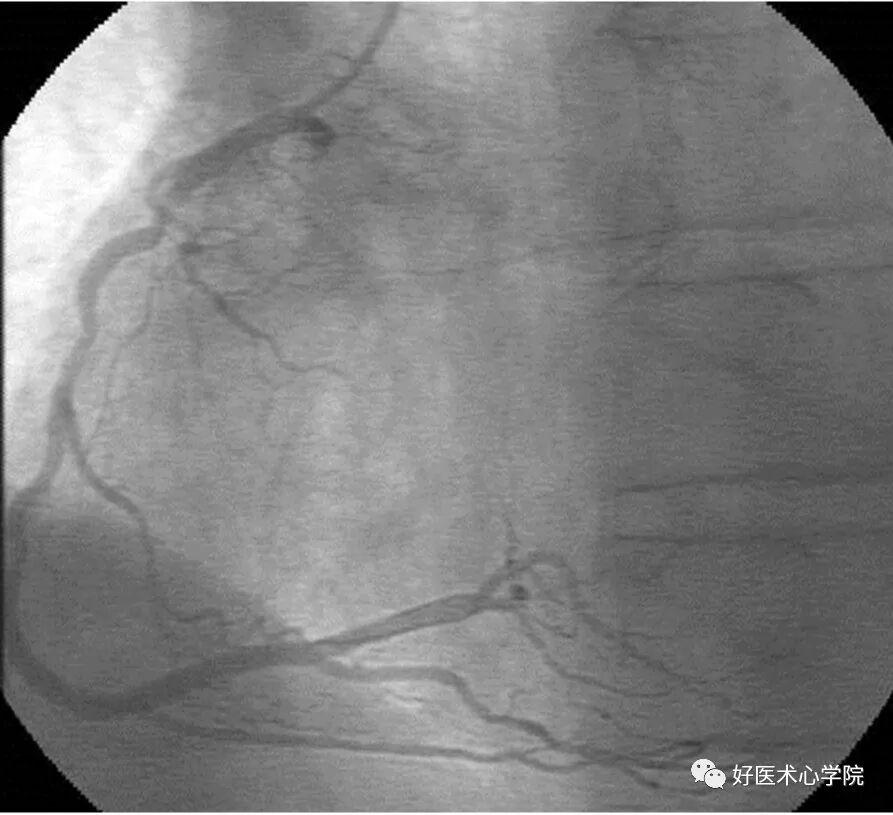

5. 心肌桥(Myocardial Bridging)

心肌覆盖冠脉所致,仅在收缩期出现某一节段冠状动脉狭窄,舒张期则恢复正常。提示该冠状动脉节段受心肌压迫。